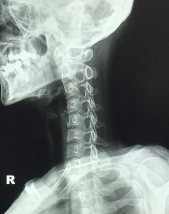

거북목 증후군 증상 원인 치료방법 알아보기

거북목 증후군 증상 원인 치료방법 등 거북목에 대한 정보를 알아보도록 하겠습니다.

거북목은 목의 자세가 앞으로 구부러지면서 등에 부담을 주는 자세로 인해 발생하는 질환입니다. 주로 스마트폰, 태블릿, 노트북 사용 등으로 인해 긴 시간을 앉아있는 경우나, 운전, 쓰기 등과 같이 앞을 보며 일하는 경우에 발생할 수 있습니다.